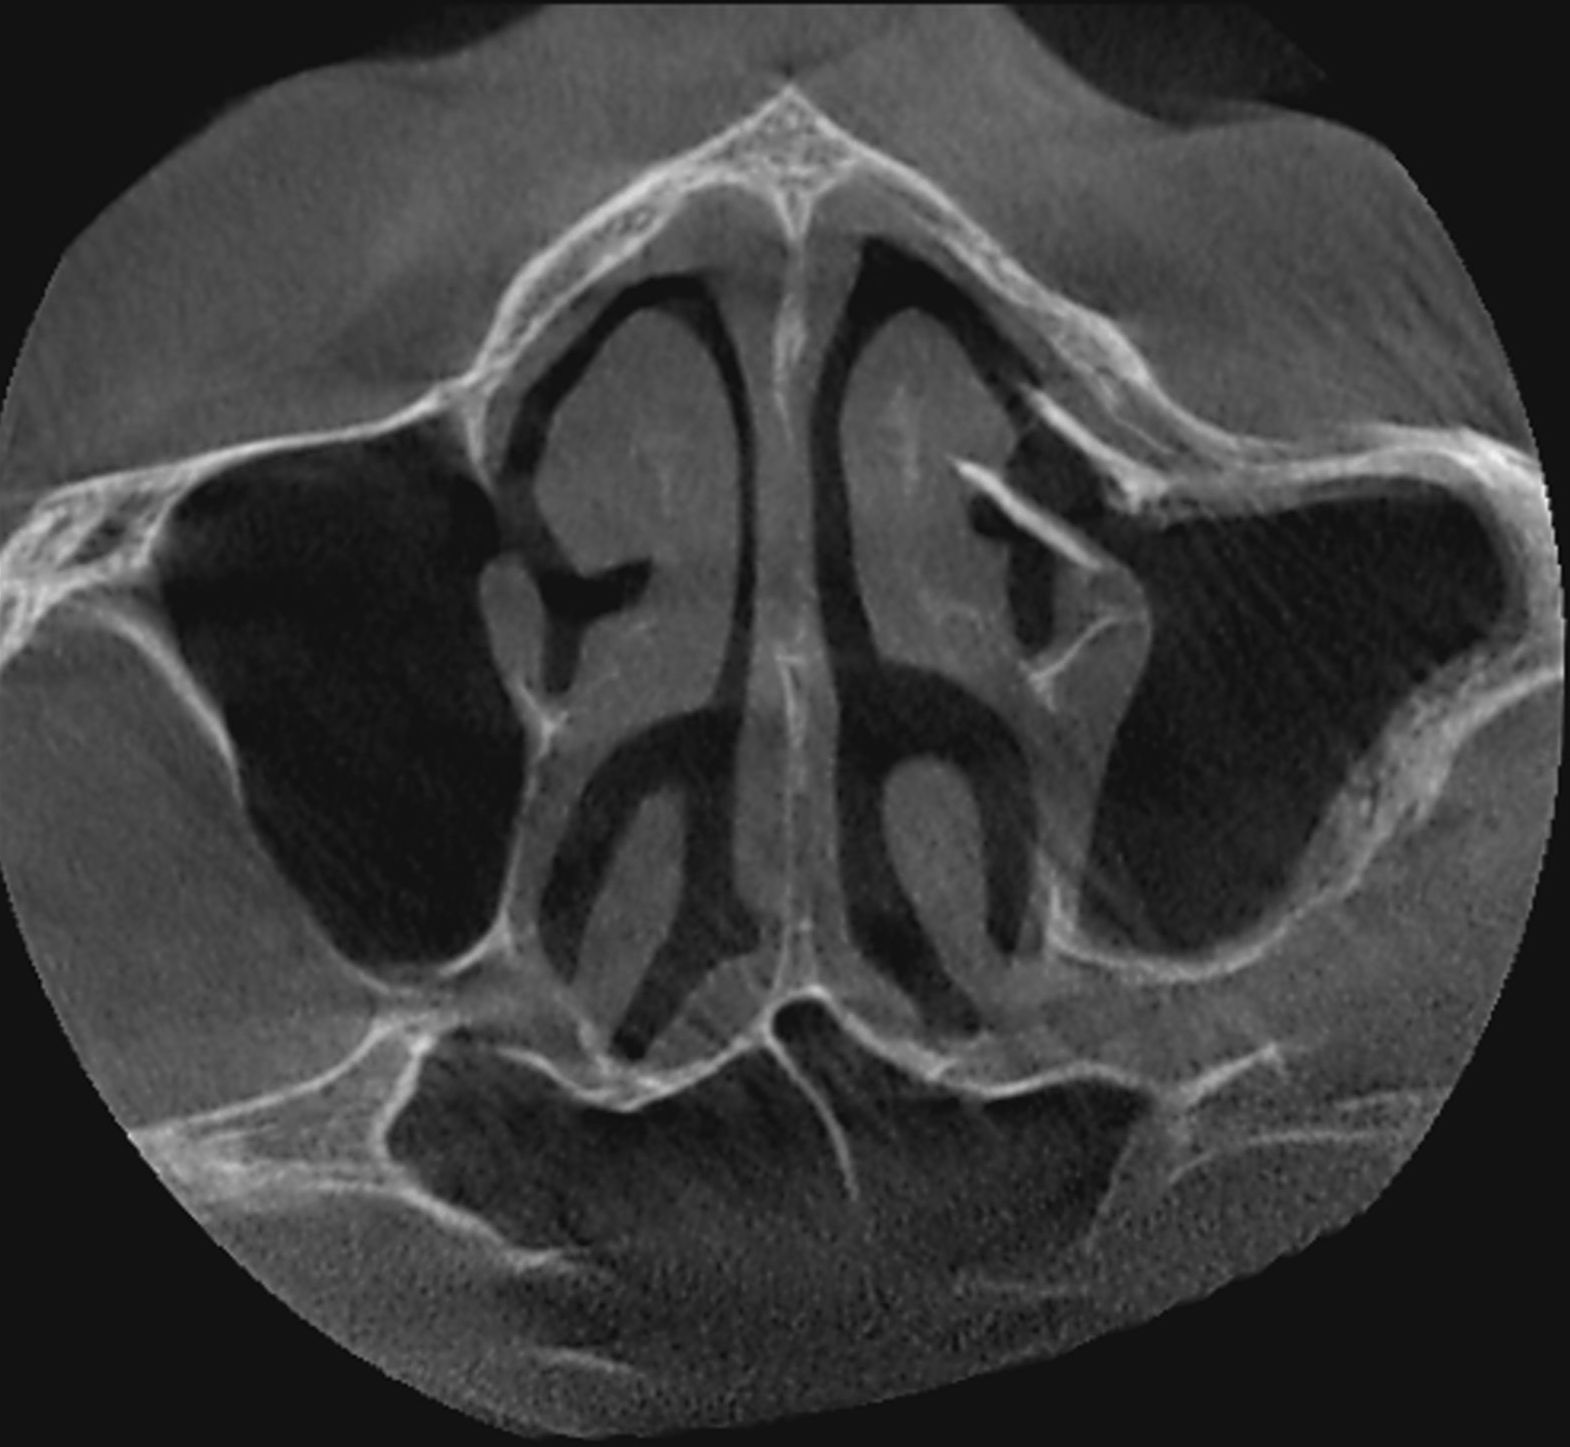

Le cone beam est une nouvelle technique de radiographie numérisée situé entre le panoramique dentaire et le scanner, il utilise un faisceau d’irradiation de forme conique d'où son nom. Cet appareil présente notamment l’avantage d’être plus précis que le panoramique dentaire et il possède une résolution similaire, voire supérieure à celle du scanner, avec en plus la possibilité d’une reconstruction numérique en 3D.

Le cone beam utilisé en pathologie dentaire et maxillo-faciale est indiqué pour l’examen des tissus minéralisés (dents, cartilages, os), il permet d’identifier les lésions osseuses, les fractures, les infections, les kystes ou les corps étrangers.

Les applications du cone beam dentaire sont donc nombreuses allant de la chirurgie buccale à l’orthodontie (télécrânes...), en passant par la chirurgie maxillo-faciale et l’ORL.

- pathologie des sinus maxillaires